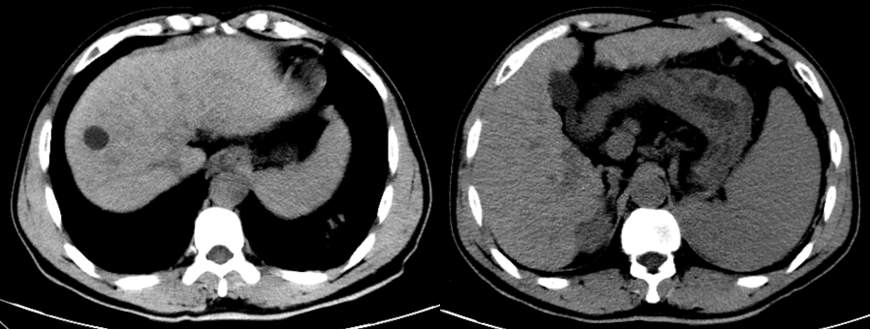

一位 60 岁的男性患者因反复解黑便 25 天来院就诊,全腹部 CT 平扫加增强检查结果令人揪心:肝右叶多发占位,大者范围约 110 mm×70 mm,考虑原发性肝癌,伴门脉右支及主干癌栓可能;同时还发现肝硬化,脾大,食管胃底静脉曲张,门静脉高压伴侧支循环开放,腹盆腔积液。追溯病史发现,早在 2019 年,该患者就已通过 CT 检查确诊肝硬化、脾大及门静脉高压伴侧支循环开放,但 6 年间未进行任何定期复查,最终错失了早期干预的机会。

图 1 患者 2019 年 CT 图像示肝硬化、脾大。